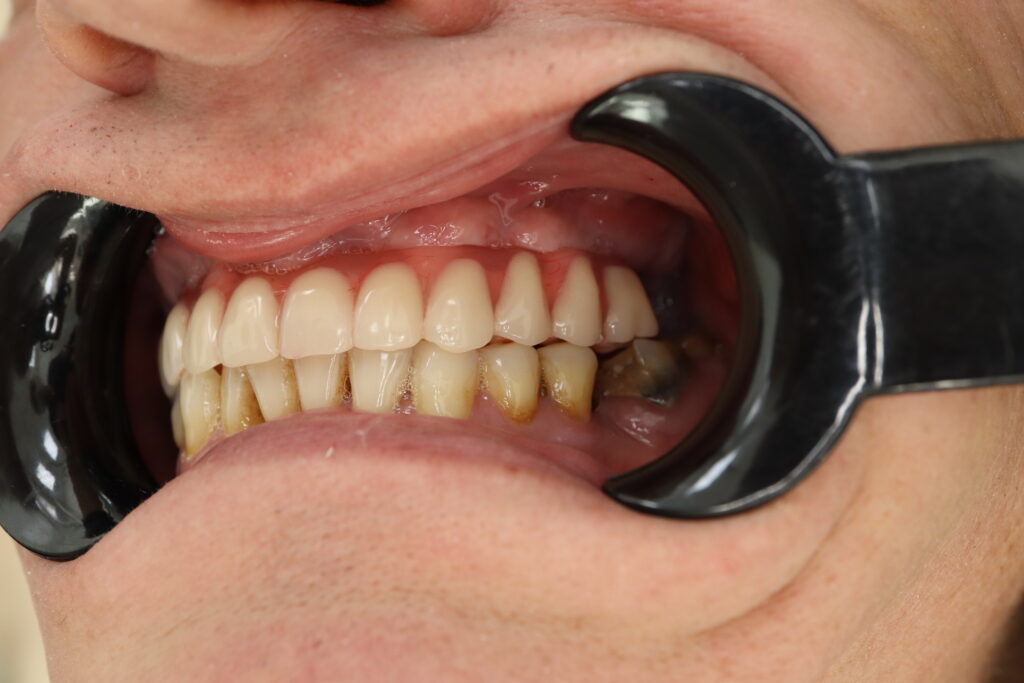

результат протезирования